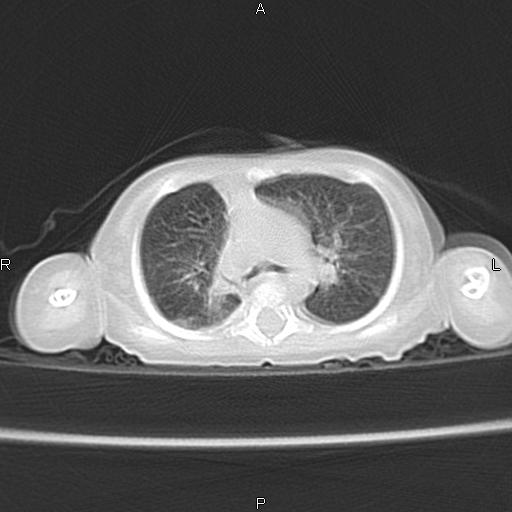

以下是引用aa13877358820在2010-7-26 12:35:00的发言:[br]男性,三个月,卧位胸片,咳嗽、气促、发热14天,两肺闻及细小水泡音。[br]